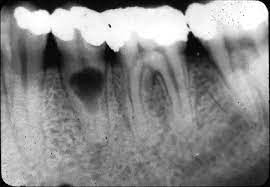

Absceso Periapical Agudo

Un absceso periapical agudo es una acumulación de pus en la punta de la raíz del diente debido a una infección.

Los pacientes suelen experimentar dolor intenso, hinchazón y fiebre.

Esta condición requiere tratamiento inmediato, como el drenaje del absceso y un tratamiento de conducto. Sin tratamiento, la infección puede propagarse a otras áreas.

Absceso Periapical Crónico

Un absceso periapical crónico es una infección prolongada en la punta de la raíz del diente que forma una bolsa de pus.

Los pacientes pueden tener dolor leve o no tener síntomas, pero notar una fístula en la encía.

El tratamiento incluye un tratamiento de conducto y, en algunos casos, una cirugía apical. Es crucial tratarlo para evitar la propagación de la infección.

Granuloma Periapical

Un granuloma periapical es una pequeña masa de tejido inflamatorio en la punta de la raíz del diente, generalmente como respuesta a una infección crónica.

Los pacientes pueden no sentir dolor, pero el área puede estar sensible al tacto.

El tratamiento de conducto es necesario para eliminar la fuente de la infección y permitir la curación del tejido.